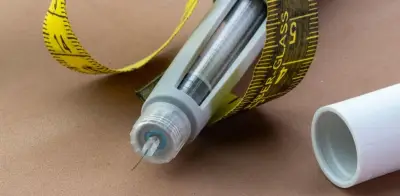

La detección temprana del cáncer podría experimentar un cambio radical gracias a un nuevo método desarrollado por científicos de la Universidad de California en Los Ángeles (UCLA). Denominado MethylScan, este innovador test sanguíneo ha demostrado capacidad para identificar múltiples tipos de cáncer, enfermedades hepáticas y anomalías en diversos órganos mediante el análisis de fragmentos de ADN que circulan en el torrente sanguíneo.

El análisis de sangre para detectar cáncer, conocido como biopsia líquida, no es una técnica nueva, pero su aplicación para identificar la enfermedad en fases iniciales ha representado históricamente un desafío significativo. Las principales dificultades radican en las bajas concentraciones tumorales en los fragmentos de ADN sanguíneo y la enorme diversidad genética del cáncer.

Lo que diferencia a MethylScan de otros métodos es su enfoque en la metilación del ADN, un proceso que involucra marcas químicas que regulan la actividad génica. "La metilación del ADN refleja el estado de salud de un tejido celular y nos proporciona información extremadamente valiosa", explica Wenyuan Li, investigador de UCLA y coautor del estudio.

El equipo de UCLA ha desarrollado una técnica innovadora que resuelve este problema mediante el uso de enzimas especializadas que eliminan selectivamente los fragmentos de ADN no metilados. Este proceso reduce drásticamente la cantidad de secuenciación necesaria, disminuyendo los costos sin comprometer la sensibilidad de los resultados.

Aunque MethylScan aún no está disponible comercialmente, se estima que su precio podría rondar los 20 dólares (aproximadamente 17 euros), lo que lo convertiría en una opción asequible para programas de detección masiva.